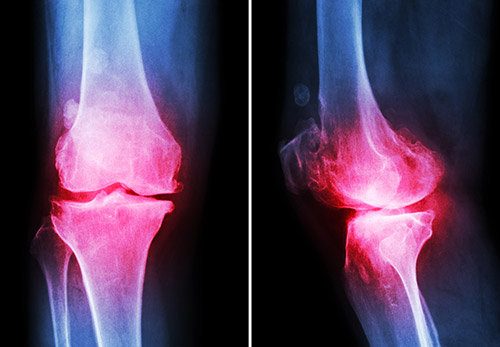

Surgeons usually have no choice but to adjust implant rotation, alignment, and fit because off-the-shelf implants are not engineered to patients’ varied anatomy. This is why some patients experience sustained pain after the surgery and why 1 out of 5 aren’t happy with their knee implants.